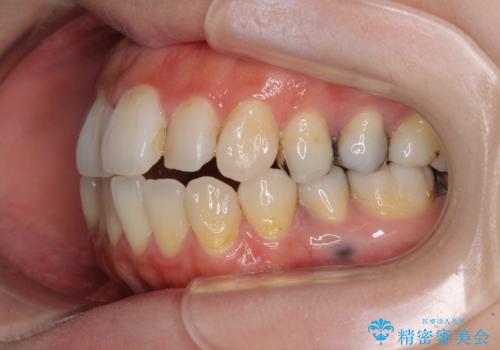

出っ歯と奥歯の欠損 ワイヤー矯正とインプラント治療

- 口元の突出感と奥歯の欠損を気にして来院された患者様です。

口元の突出感改善には、上下左右の第一小臼歯4本を抜歯し、奥歯の欠損部には矯正治療の途中でインプランを埋入していくこととしました。